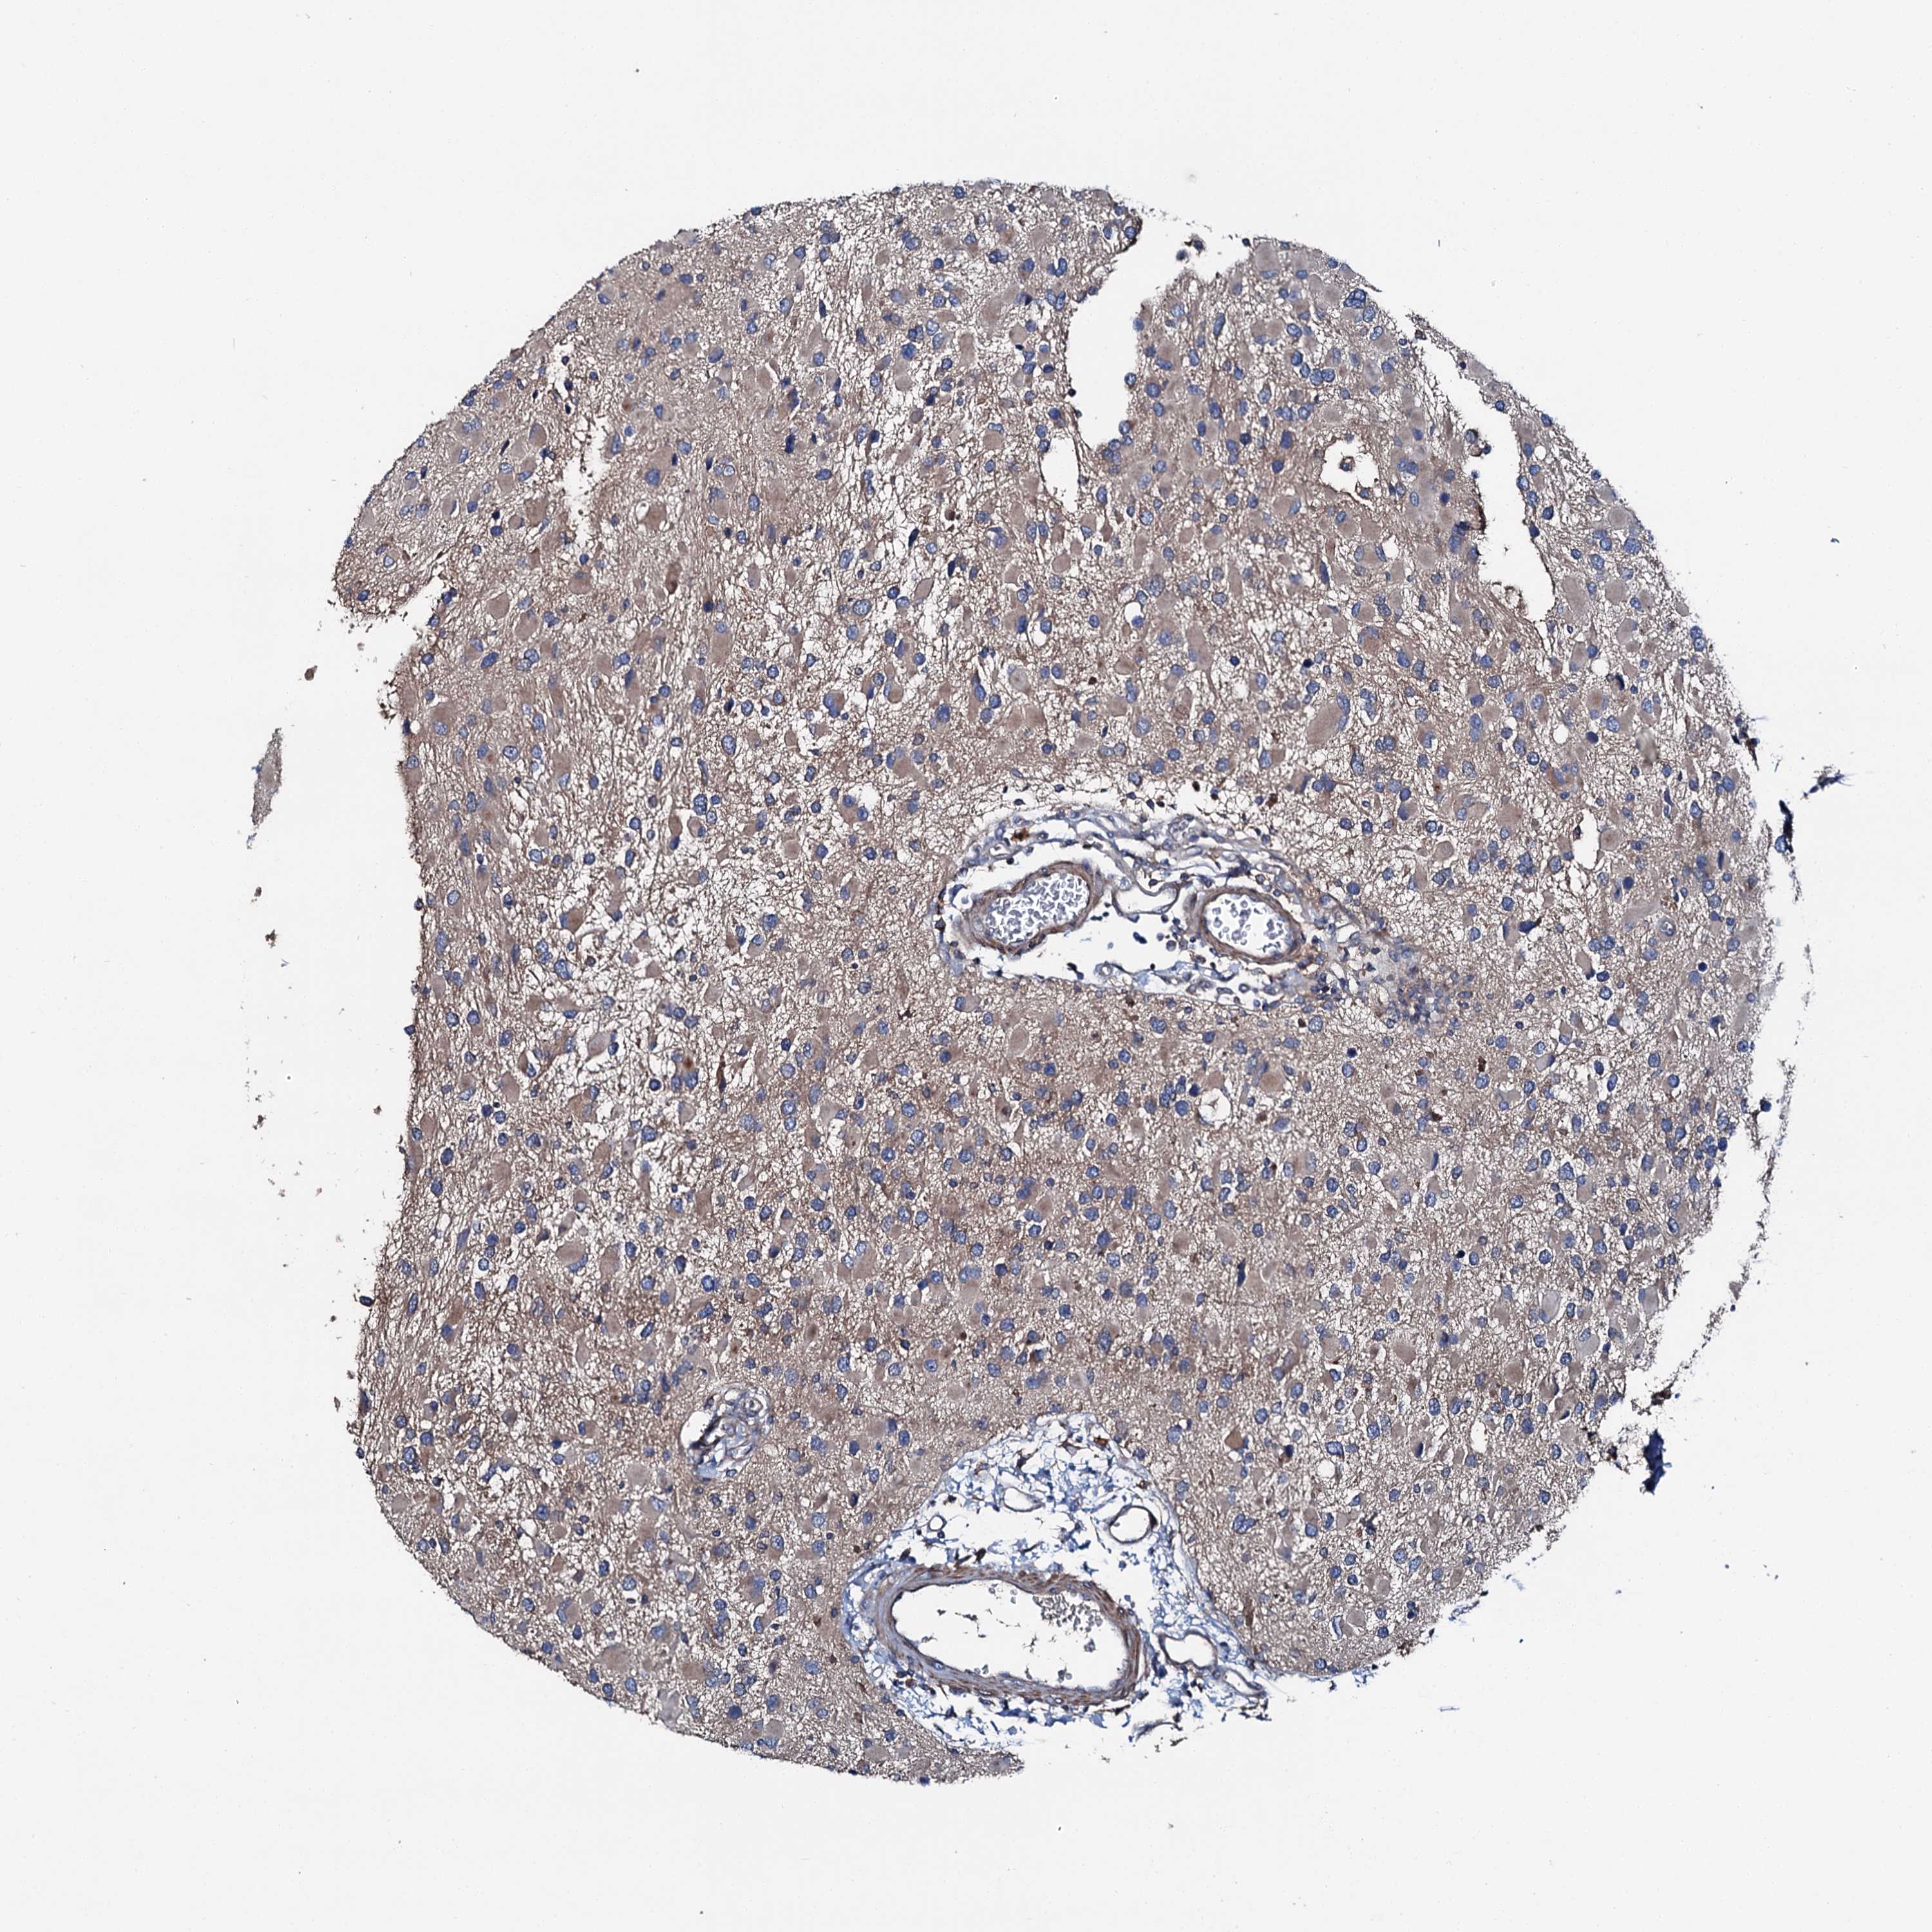

GLIOMA - Protein expressioni

A mouse-over function shows sample information and annotation data. Click on an image to view it in a full screen mode. Samples can be filtered based on level of antibody staining by selecting one or several of the following categories: high, medium, low and not detected. The assay and annotation is described here.

Antibody stainingi

Antibody staining in the annotated cell types in the current human tissue is reported as not detected, low, medium, or high, based on conventional immunohistochemistry profiling in selected tissues. This score is based on the combination of the staining intensity and fraction of stained cells.

Each image is clickable and will lead to virtual microscopy that enables deeper exploration of all samples and also displays staining intensity scores, fraction scores and subcellular localization as well as patient and tissue information for each sample.

Antibody HPA039390

Staining

High

Medium

Low

Not detected

Intensity

Strong

Moderate

Weak

Negative

Quantity

>75%

75%-25%

<25%

None

Location

Nuclear

Cytoplasmic/membranous

Cytoplasmic/membranous,nuclear

Glioma, malignant, High grade

Glioma, malignant, Low grade